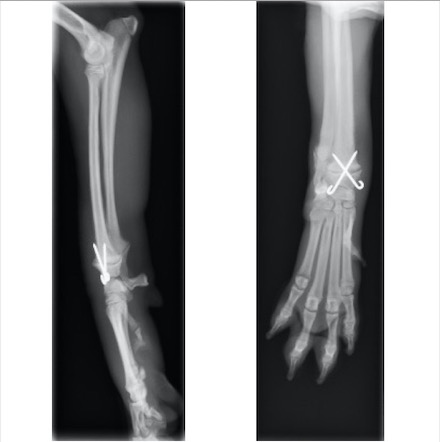

単純X線画像検査上、側面像では大きな左右差は認められませんでしたが、背掌像にて右前肢の軟部組織の腫脹と成長板の間隙が広くなっていることから橈骨遠位成長板骨折(Salter-Haris Type1)と診断し、外科的処置を行いました。

初心時のX線画像検査初見 赤矢印:軟部組織の主張、黄矢印:橈骨遠位成長板(左前肢と比較すると、成長板の隙間が広くなっております)

キルシュナーワイヤーを用いたクロスピン法にて整復しました

術後約1ヵ月後 挙上が認められなくなり、患肢に負重をかけて歩行ができるようになったため、キルシュナーワイヤーを抜去しました